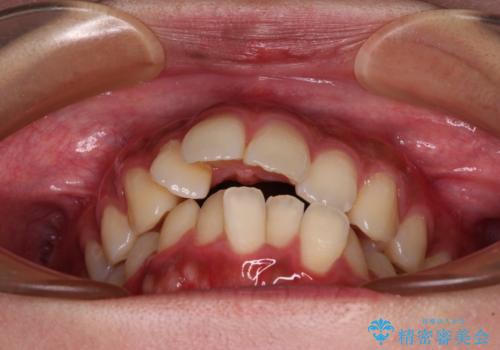

- 前歯の突出感とデコボコを気にして来院された患者様です。

奥歯の噛み合わせをみると、上顎歯列が全体的に前突している状態であり、この咬み合わせのまま歯列を整えると出っ歯になってしまう可能性がありました。

アンカースクリューと補助装置を使用して上顎大臼歯を遠心移動させることで咬み合わせを改善し、更には口元の突出感を改善するために上下左右の小臼歯4本を抜歯し、ワイヤー装置によりデコボコを解消しながら口元の突出感も改善していくこととしました。